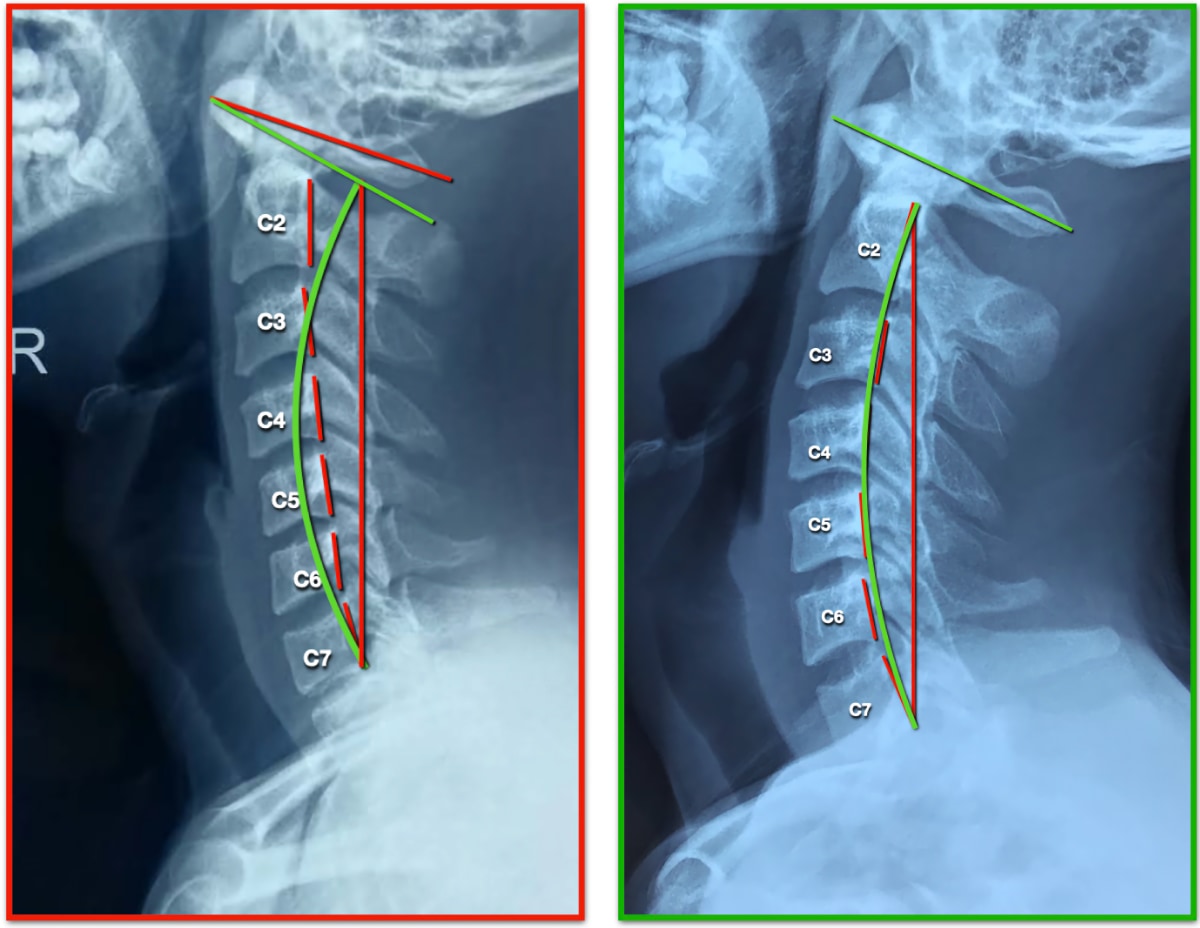

• Forward Head

Continue reading

• Side Neck Curve Case 18Y

• Side Neck Curve Case 52Y